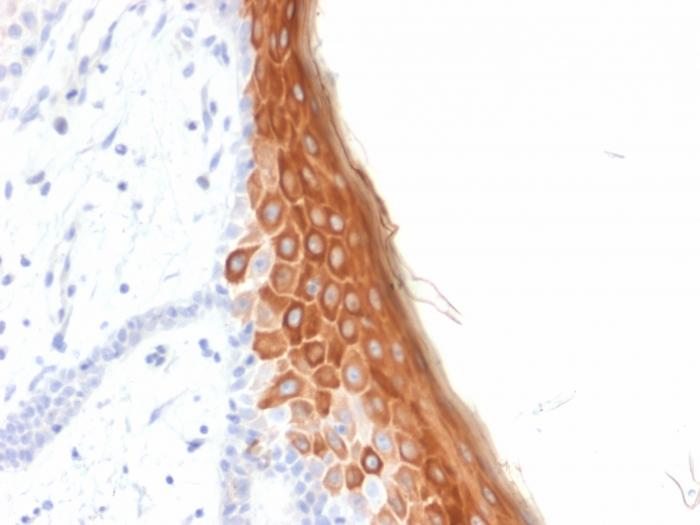

This MAb recognizes a protein of 56.5 kDa, identified as cytokeratin 10 (CK10). CK10 is expressed in all suprabasal layers of the epidermis. In the epidermis, expression of CK10 strictly parallels the extent of differentiation; it is absent in the basal layer, appears in the first suprabasal layers and increases in concentration towards the granular layer. However, CK10 is rarely detected in early stages of vulvar squamous carcinomas (tumors less than 2 cm, clinical stage I) regardless of the tumor grade. In larger and more advanced tumors (greater than 2 cm, clinical stages II and III), CK10 is detected very frequently. Expression of CK10 is related to maturation of malignant keratinocytes, being preferentially detected in more-differentiated parts.Primary antibodies are available purified, or with a selection of fluorescent CF® Dyes and other labels. CF® Dyes offer exceptional brightness and photostability. Note: Conjugates of blue fluorescent dyes like CF®405S and CF®405M are not recommended for detecting low abundance targets, because blue dyes have lower fluorescence and can give higher non-specific background than other dye colors.

A431, HeLa, MCF7 cells. Esophagus or tonsil.

Epidermal cells

Squamous cell carcinoma

IHC, FFPE (verified)